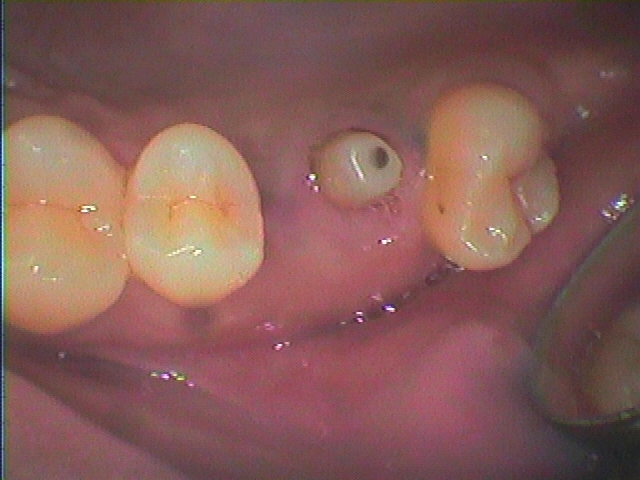

右上6番のインプラント埋入。| |広島市安佐南区の歯科医院 右上6番のインプラント埋入。 トップ お知らせ・ブログ 右上6番のインプラント埋入。 右上6番のインプラント埋入。 Web診療予約 初めての方へ 選ばれ続ける理由 院内設備について 歯が痛いしみる一般歯科 歯がぐらぐらする歯周病 健康な歯を保ちたい予防歯科 子供の虫歯予防をしたい小児歯科 銀歯をセラミックに審美歯科 白い歯を目指しませんか?ホワイトニング 矯正専門医がいるので安心矯正歯科 抜けた歯を補いたいインプラント・入れ歯 医院案内 スタッフ紹介 メリィハウス歯科クリニックオフィシャルホームページ ラベンダー歯科クリニックオフィシャルホームページ お知らせ・ブログ ホーム 診療科目 一般歯科 歯周病治療 予防治療 小児歯科 審美治療 ホワイトニング 矯正歯科 入れ歯・インプラント マウスピース矯正 初めての方へ 院長・スタッフ 設備紹介 医院案内・アクセス メニューを閉じる